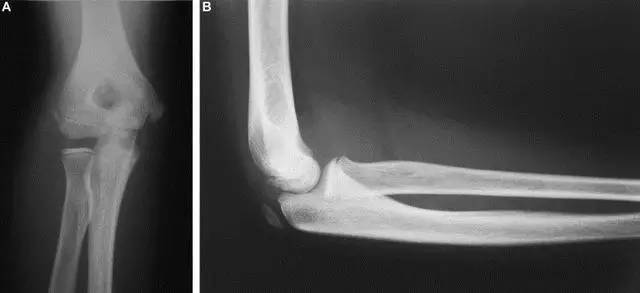

Kocher-Lorenz 骨折(来源:The often-missed Kocher-Lorenz elbow fracture. Revue de Chirurgie Orthopédique et Traumatologique, Volume 95, Issue 7, November 2009, Pages 658-661)

单纯肱骨小头骨折。